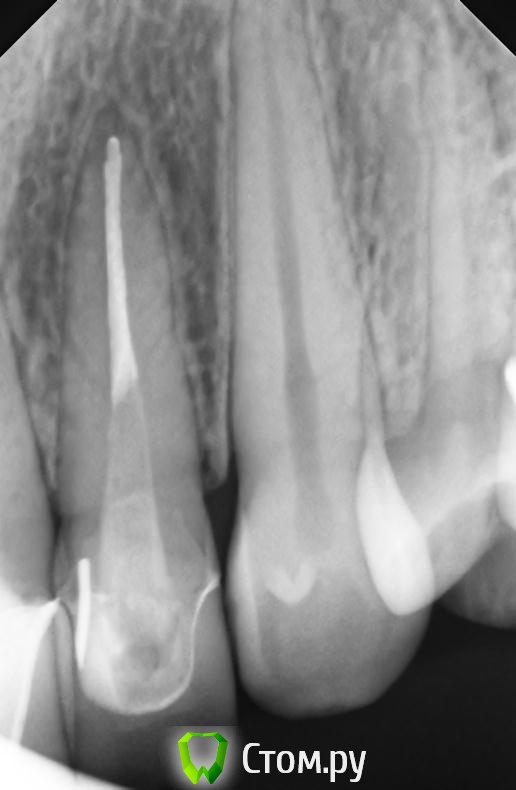

markoFFka Опубликовано 22 ноября, 2013 Поделиться Опубликовано 22 ноября, 2013 Прошу посмотреть снимок!22 зуб беспокоит после пломбирования каналов при накусывании в течение месяца.Смущают темные линии посередине корня.Не может ли это быть трещиной?или это коллатерали? вообще склоняюсь к тому,что осталось недопакована верхушка,и боли из-за этого.но все-таки смущают эти полосы посередине корня... Ссылка на комментарий

M@estro Опубликовано 22 ноября, 2013 Поделиться Опубликовано 22 ноября, 2013 Перелома нет? Есть сомнения по снимку Ссылка на комментарий

markoFFka Опубликовано 22 ноября, 2013 Автор Поделиться Опубликовано 22 ноября, 2013 Перелома нет? Есть сомнения по снимкуну меня этот же вопрос собственно и интересует.но на двойке с другой стороны,как мне кажется,тоже подобные полосы.вот снимок 12. Ссылка на комментарий

Kivilgar Опубликовано 23 ноября, 2013 Поделиться Опубликовано 23 ноября, 2013 Да,конечно пародонт)21 на снимке в девятом сообщении есть вместе с 11 и 12. 11 и 21 лечены очень много лет назад,никогда не беспокоили.отдельный снимок 11 и 12 делали летом,сейчас не могу выложить.в данном случае точно не они.Перкуссия положительна именно 22го.Тогда только и остается http://s57.radikal.ru/i156/1311/fd/209d7896d0be.jpg 6 Ссылка на комментарий

Scrabble Опубликовано 24 ноября, 2013 Поделиться Опубликовано 24 ноября, 2013 (изменено) СВШ установлен не по протоколу: надо бы за 3-4 мм до верхушки. Хотя по статистике, которую приводил Соломонов на лекции "Endoprostodontic relationship" переломы с СВШ встречаются крайне редко. Просто при таком позиционировании штифта, как в вашем случае, реставрация на СВШ получается подвижной при латеральных нагрузках-что, собственно, может быть причиной болей. Изменено 24 ноября, 2013 пользователем Scrabble 1 Ссылка на комментарий